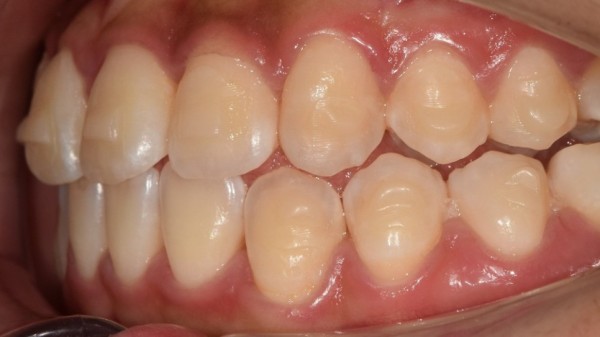

이 학생은 앞니가 삐뚤어져 있어서 이 부분을 개선하고 싶었습니다.

앞니 총생때문에 저희 성남치과 더서울치과를

찾아오셨다고 하셨는데요. 엑스레이 사진을 보아도

앞니 총생 말고는 다른 부분의 문제가 보이지는 않았습니다.

이 학생은 초기 예상한대로 약 1년정도의 교정기간이 걸렸으며

최종 모습을 보면 앞니가 잘 펴져있는것을 확인할 수 있습니다.

This student took about a year of proofreading as expected

If you look at the final appearance, you can see that the front teeth are well spread out.